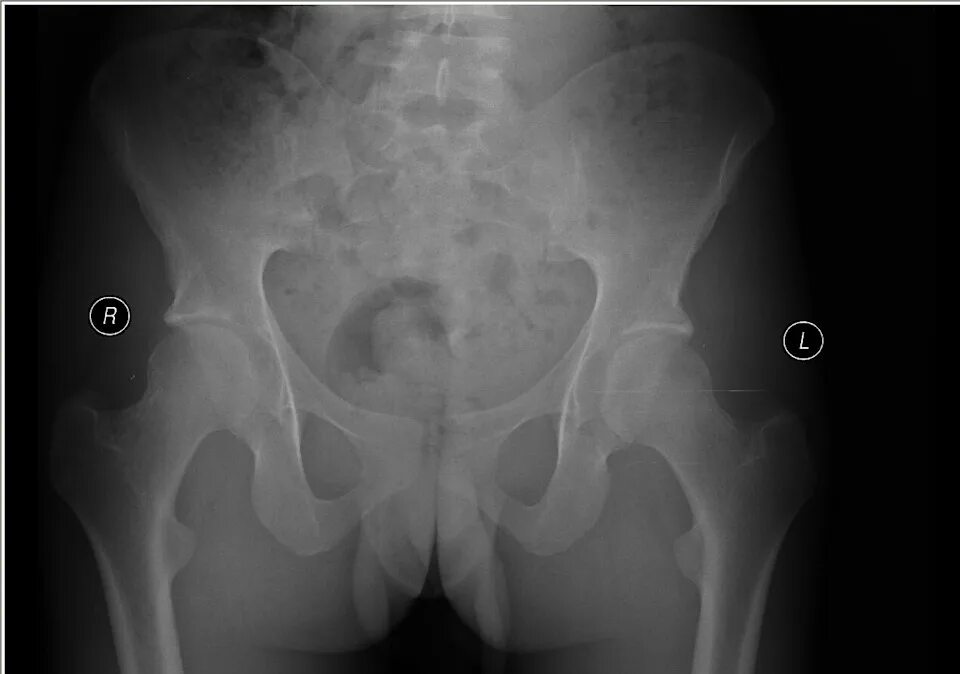

Снимок копчика